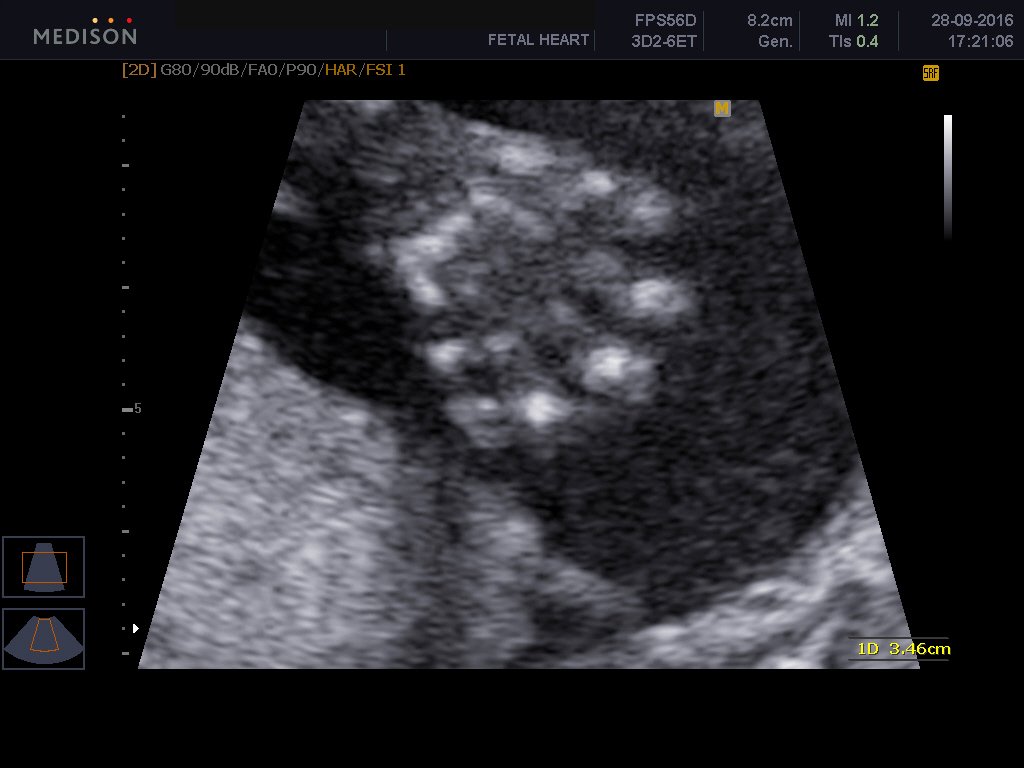

To υπερηχογράφημα β επιπέδου είναι ειδικό υπερηχογράφημα το οποίο εκτελείται από εξειδικευμένο ιατρό και με το οποίο ελέγχεται λεπτομερώς η ανατομία του εμβρύου. Γίνεται όπως όλα τα υπερηχογραφήματα δια μέσου της κοιλιακής χώρας της εγκύου και είναι απόλυτα ανώδυνο.Είναι δυνατόν το υπερηχογράφημα να απεικονίσει σοβαρές συγγενείς ανωμαλίες του εμβρύου καθώς και ελαφρές ανατομικές βλάβες. Επίσης αναγνωρίζει υπερηχογραφικά σημάδια , τα καλούμενα markers , με τα οποία υποπτευόμαστε σοβαρά χρωμοσωμιακά σύνδρομα εμβρύου, όπως το σύνδρομο Down, την trisomy 18 και trisomy 13. Γίνεται έλεγχος του πλακούντα εκτιμάται το αμνιακό υγρό καθώς και η προβολή του εμβρύου και ο τράχηλος της μήτρας και ειδικά το μήκος τραχήλου μας δίνει πληροφορίες όσον αφορούν τον πρόωρο τοκετό.

Ελέγχεται το κρανίο, ο εγκέφαλος, το πρόσωπο, η καρδιά, τα χέρια, τα πόδια, η σπονδυλική στήλη, η ουροδόχος κύστη του μωρού. Μερικές συγγενείς βλάβες που μπορεί να αναγνωρίσει το υπερηχογράφημα είναι οι εξής: Ανεγκεφαλία, ανοιχτές βλάβες νωτιαίου σωλήνα , χειλεοσχιστία -λαγόχειλος, διαφραγματοκήλη, γαστρόσχιση , εξόμφαλος, σοβαρές καρδιακές συγγενείς ανωμαλίες, αγενεσία νεφρών, πολυκυστικούς δυσπλαστικούς νεφρούς, θνησιγενείς σκελετικές δυσπλασίες.